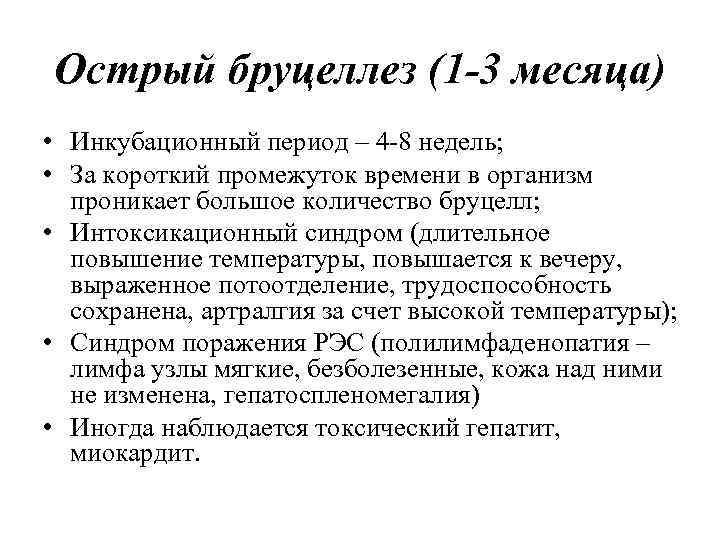

Острый бруцеллез (1 -3 месяца) • Инкубационный период – 4 -8 недель; • За короткий промежуток времени в организм проникает большое количество бруцелл; • Интоксикационный синдром (длительное повышение температуры, повышается к вечеру, выраженное потоотделение, трудоспособность сохранена, артралгия за счет высокой температуры); • Синдром поражения РЭС (полилимфаденопатия – лимфа узлы мягкие, безболезенные, кожа над ними не изменена, гепатоспленомегалия) • Иногда наблюдается токсический гепатит, миокардит.

Острый бруцеллез (1 -3 месяца) • Инкубационный период – 4 -8 недель; • За короткий промежуток времени в организм проникает большое количество бруцелл; • Интоксикационный синдром (длительное повышение температуры, повышается к вечеру, выраженное потоотделение, трудоспособность сохранена, артралгия за счет высокой температуры); • Синдром поражения РЭС (полилимфаденопатия – лимфа узлы мягкие, безболезенные, кожа над ними не изменена, гепатоспленомегалия) • Иногда наблюдается токсический гепатит, миокардит.